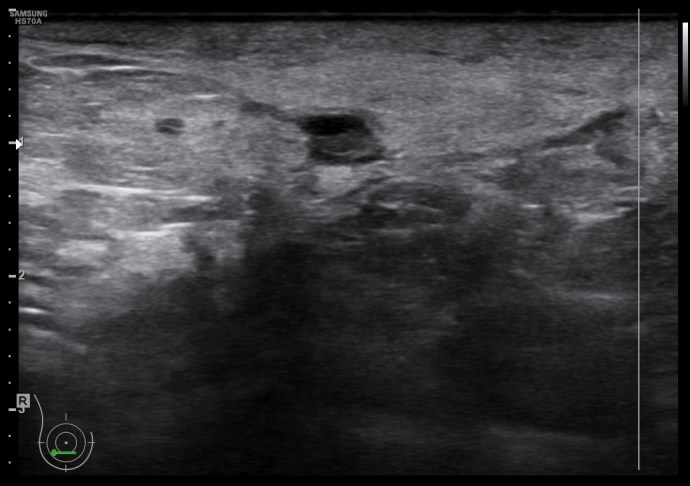

En la imagen 3 puedes ver un absceso, complicación de una mastitis, cuyo aspecto es el de una colección anecoica, que si observas, quieres buscar la superficie de la piel. La imagen 4 y 5 es el estudio de la lesión en trasnverso u otro plano y el estudio doppler buscando posible vascularización a ese nivel.

En las mastitis, al ser procesos infecciosos, no es raro ver gánglios intramamarios aumentados de tamaño o reactivos que hayan perdido su centro graso. En este caso, en localización muy próxima. Observa el aspecto habitual en forma de judia con centro hiperecogénico graso y corteza hipoecogénica, imagen 4.